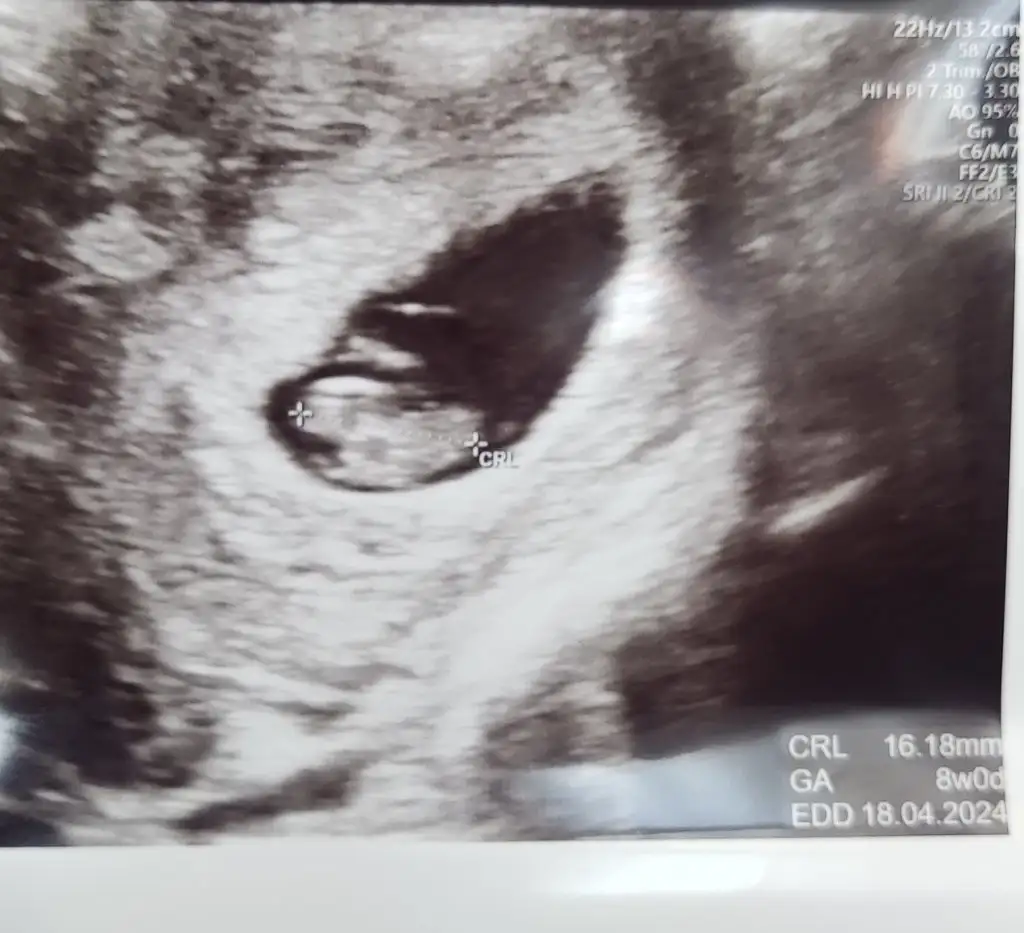

Merhaba benim içinde bir tahminde bulunabilir misiniz ?

Merhaba karından ultrason 8 haftalık banada tahminde bulunur musunuz ?